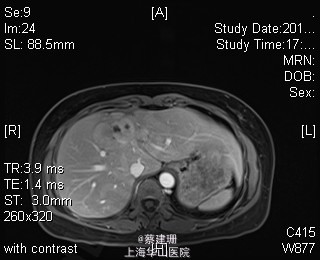

主诉:平滑肌肉瘤、肝转移癌术后,发现肝多发转移2月余。 现病史:患者3年前外院检查发现后腹膜肿瘤,外院行后腹膜肿瘤切除术后,术后病理为:平滑肌肉瘤,2013年12发现肝左叶转移癌,外院行肝左叶肿瘤切除术,术后病理为:梭行平滑肌肉瘤。2月余前患者复查发现肝脏多发转移,2015-4月肝脏MRI:肝脏多发转移。现患者无恶心、呕吐,无呕血、黑便,无皮肤巩膜黄染,无剧烈腹痛发作。现为进一步诊治收住入院。

查体:锁骨上淋巴结未扪及肿大;腹部平坦,可见陈旧性手术疤痕。未见肠型、胃型蠕动波,腹软,无压痛及反跳痛,无肌卫,肝脾肋下未及。Murphy’s 征(-),肝区叩击痛(-),肾区叩击痛(-);移动性浊音阴性。 辅查:2015-4月肝脏MRI:肝脏多发转移。

诊断 :1、多发肝转移癌 2、后腹膜平滑肌肉瘤术后 3、肝转移癌术后 处理:取右侧肋缘下切口,左侧延长,逐层切开进腹,探查腹腔:见上腹部粘连,仔细游离上腹部腹腔粘连,探查见无腹水,胃、肠、胰、脾及盆腔脏器未及异常,腹腔未见明显转移结节;肝脏无硬化。肝门淋巴结无肿大,门静脉主干无栓子。肿瘤多枚,最大两枚位于肝右叶VI段,肿瘤大小约7*6*5cm。V段肿瘤直径约5cm。左内叶肿瘤多枚,直径0.5-4cm,紧贴第一肝门。左外叶肿瘤多枚,直径1-3cm,肿块质韧,边界尚清,有包膜。术中诊断为转移性肝癌,决定行左半肝切除,肝右叶特殊肝段切除。